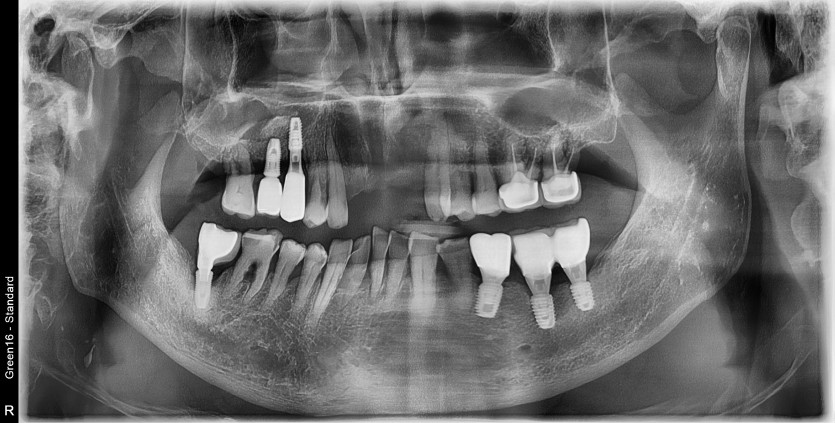

#37 타원 임플란트 제거 후

임플란트 수술+치조골이식술 시행하였습니다.